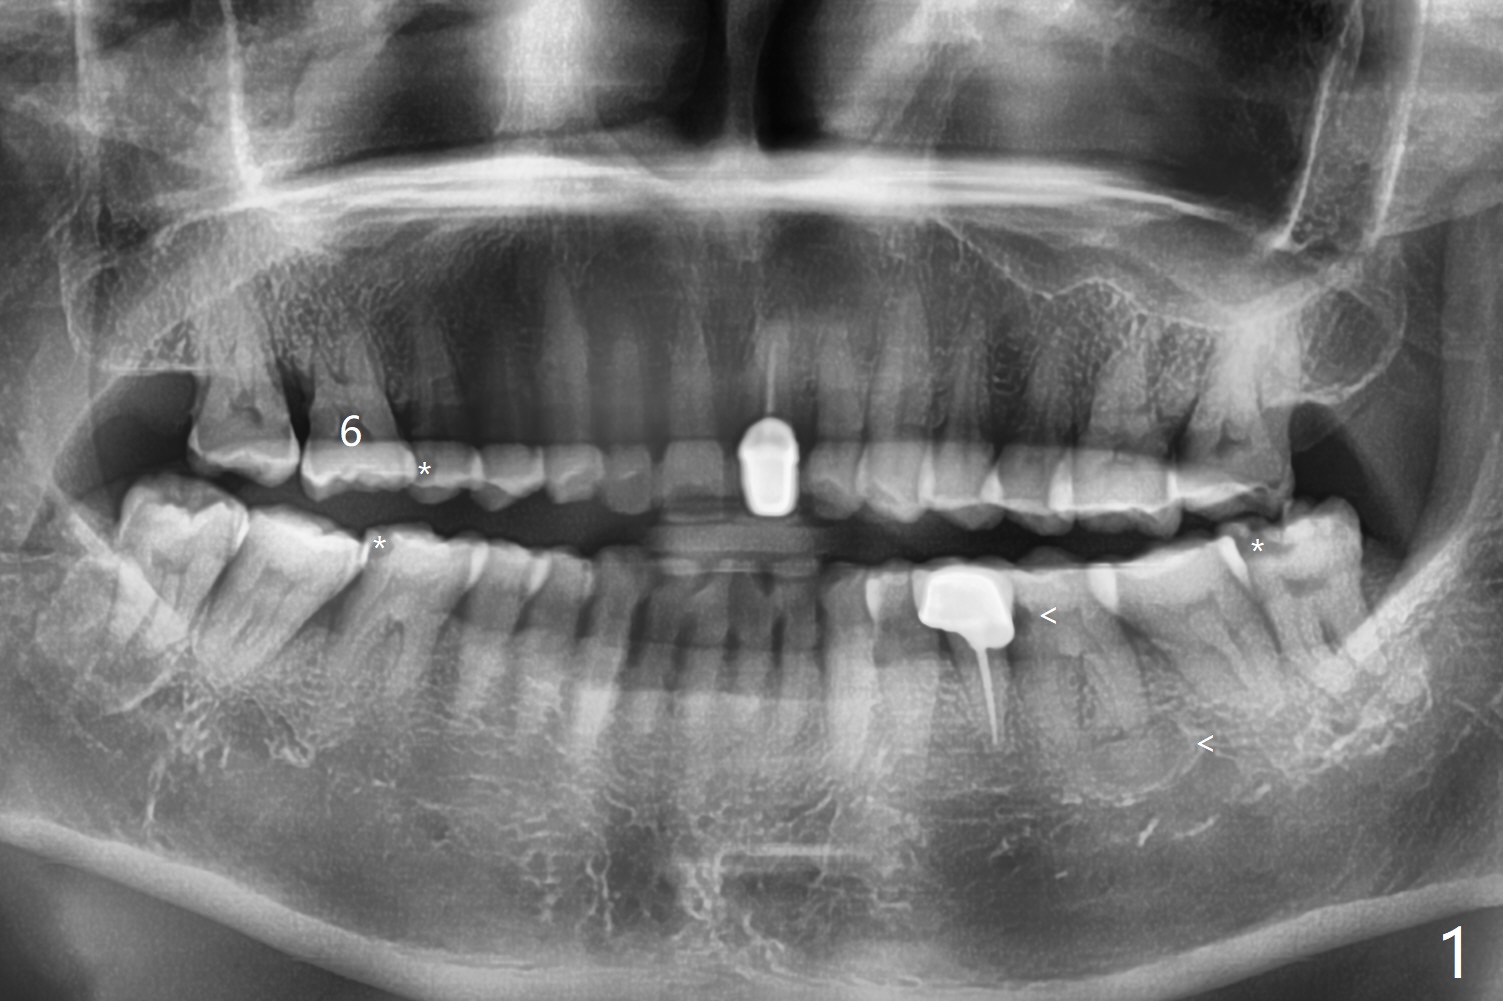

57岁女爱咬硬的东西,多个牙尖断裂(图一:*),由于左下6近中龋齿,远中根尖周炎(<),最近在右边咀嚼多,突然右上6出现严重疼痛,检查发现近中腭侧牙尖折裂,病人要求拔除,可能出血多,没有骨质吸收,骨粉好像没有填入腭侧窝,而近中颊侧,远中颊侧窝(图二:MB, DB)根尖部分充填少。今后拔牙清创采血后,每个牙槽窝里塞入含1:50,000肾上腺素小纱布,压迫止血,开始输入少量骨粉,用细的器械压入牙槽窝深部。术后一周牙周敷料脱落,伤口正常愈合(图三,四)。